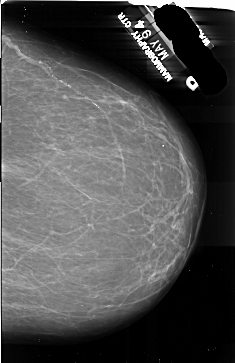

A_1014_1.RIGHT_MLO

RIGHT_MLO LINES 6916 PIXELS_PER_LINE 5596 BITS_PER_PIXEL 16 RESOLUTION 42 NON_OVERLAY